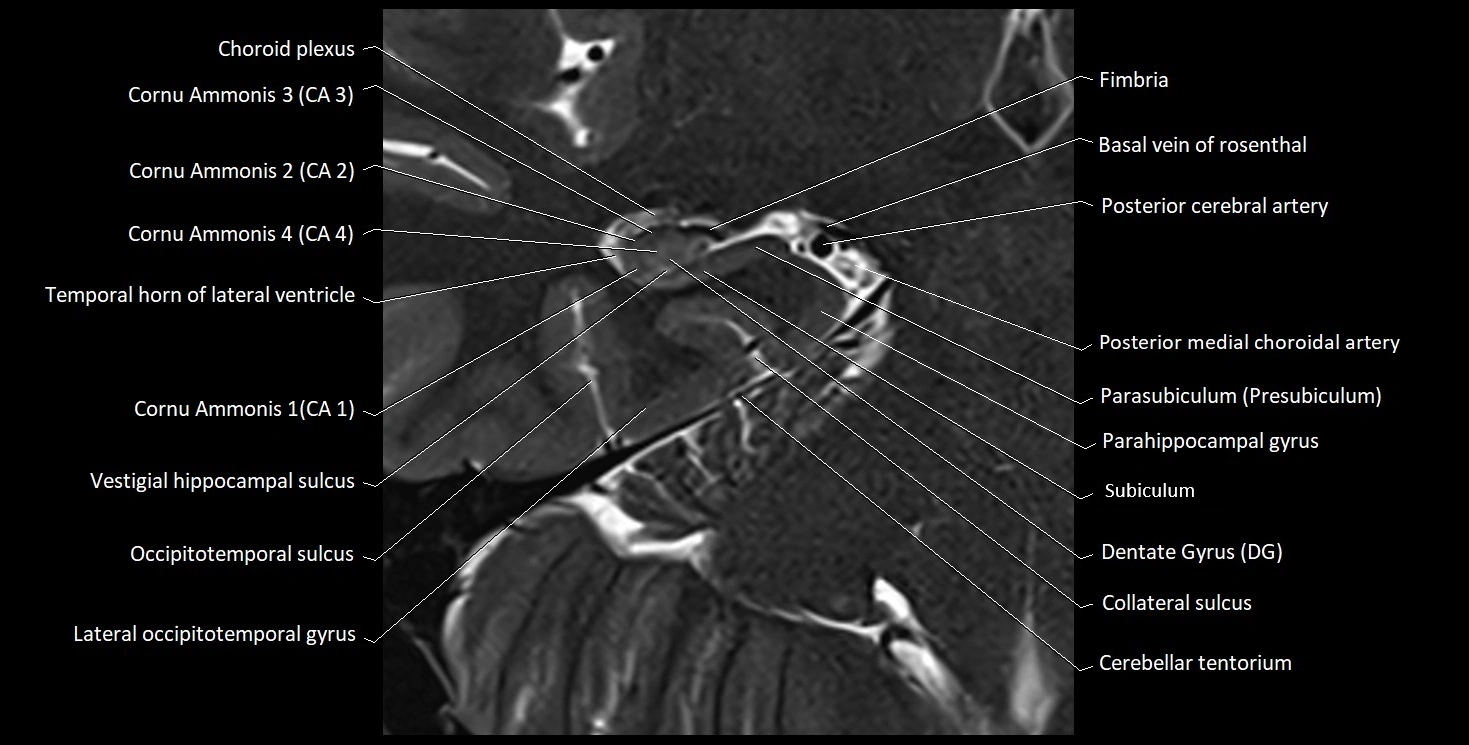

MRI images

image